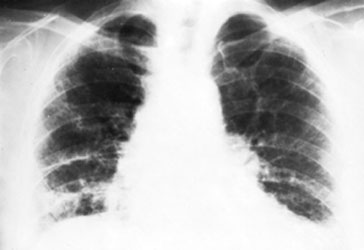

The chest x-rays presented show diffuse, severe interstitial infiltrates

without hilar adenopathy. Although sarcoidosis may produce this radiographic

picture, it is also compatible with idiopathic interstitial pneumonitis,

hypersensitivity pneumonitis, collagen vascular disease, inhalation of

inorganic dusts, and many other processes. The degree of respiratory system

dysfunction demonstrated by this patient necessitates rapid evaluation and a

definitive histologic diagnosis so that appropriate therapy can be initiated.

Angiotensin converting enzyme levels, although elevated in many patients with

sarcoidosis, are not sufficiently sensitive or specific to replace tissue

biopsy in the workup of persons with interstitial infiltrates. Although biopsy

of extrapulmonary tissue may demonstrate noncaseating granulomas in patients

with sarcoidosis, such biopsies may be negative in patients with active

disease. A pathologic diagnosis is absolutely required in patients presenting

with interstitial lung disease of uncertain etiology. Fiberoptic bronchoscopy

should be performed to rule out infection or malignancy; an accompanying

transbronchial biopsy may yield a diagnosis about 25 percent of the time.

Bronchoalveolar lavage to assess the degree of inflammation may be helpful in

monitoring disease activity, but its precise role in interstitial lung disease

has not been defined. Despite its relatively low yield, the relatively low

risk makes an attempt at transbronchial biopsy reasonable before definitely

obtaining tissue at open lung biopsy.